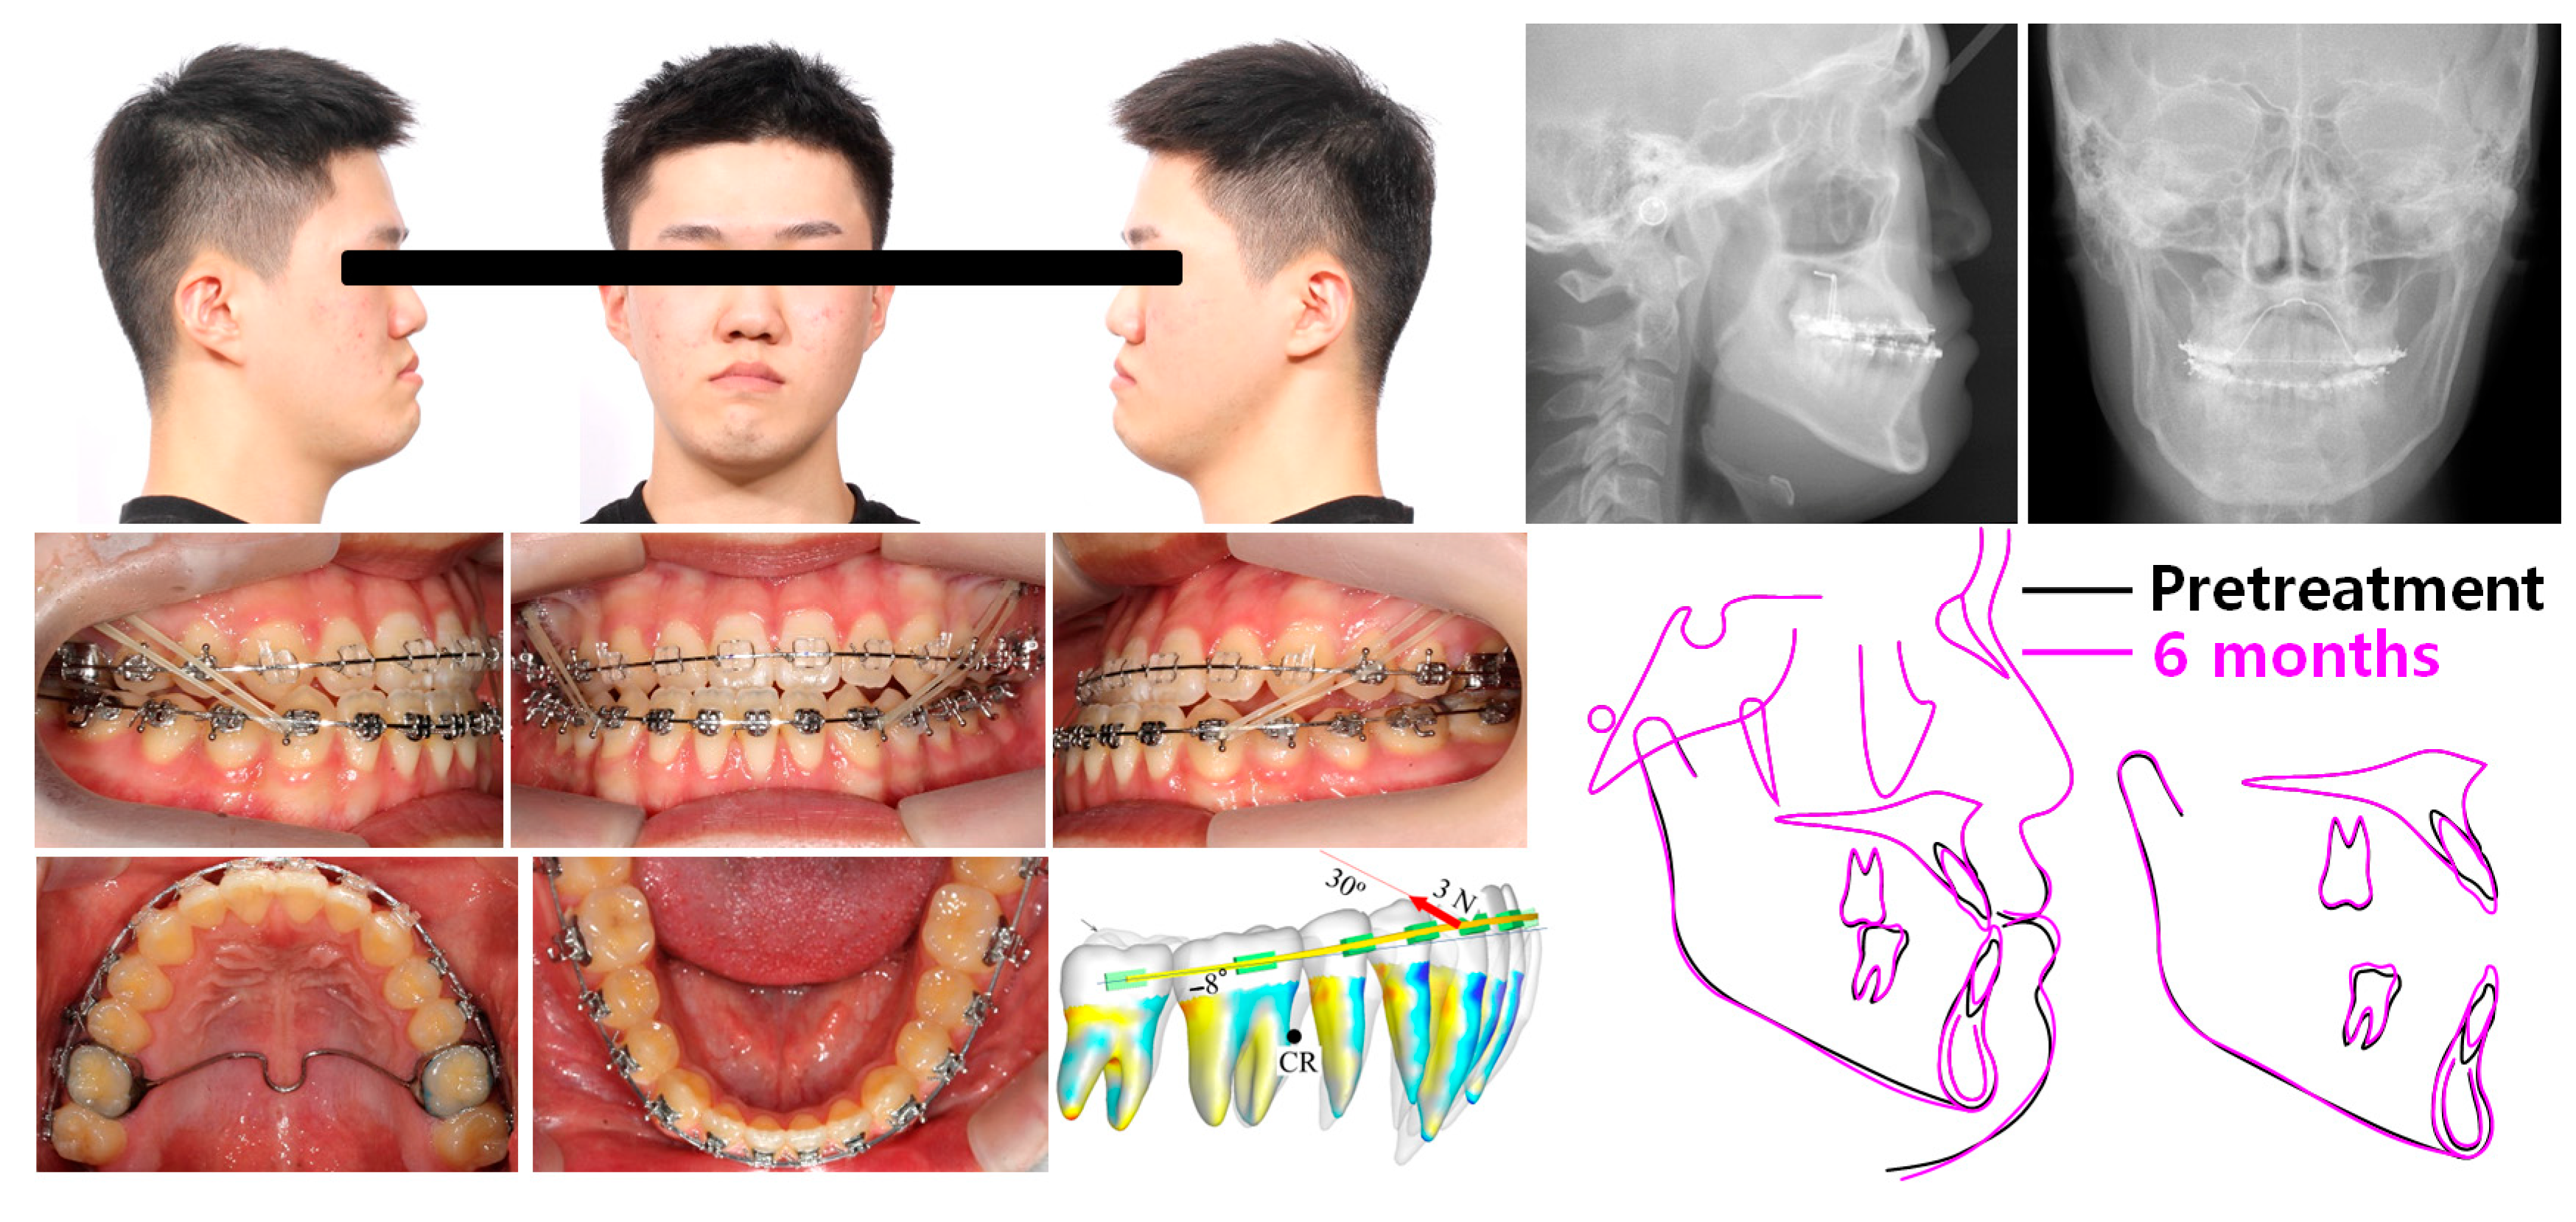

2.1. Diagnosis and Etiology

2.4. Treatment Progress